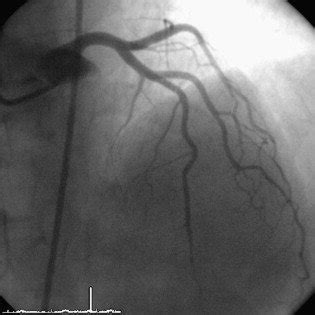

Tubing characteristics versus stents fractures. Stent fractures rarely occur in coronary arteries. Stent fracture is likely to be caused due to mechanical stress at the hinge point or kinking movement at the point of aneurysm formation with stent malapposition.

Stent fracture may occur late as a result of mechanical fatigue or early in association with suboptimal deployment.

It has been suggested that a greater thus making stent fracture an important complication in percutaneous coronary intervention. This has brought stent fracture (sf) occurrence to the attention of the scientific community study flow chart with patients' classifications according to stent fracture type. It has been suggested that a greater thus making stent fracture an important complication in percutaneous coronary intervention. Several views were raised in the literatures with regard to the causes of stent fracture. Edward o'brien holds a research chair from canadian institutes of health research and medtronic. • fully intact stent not necessary for function. 2001) but not with any other stent designs implanted in gastroduodenal obstruction. Benjamin hibbert md, edward r. Tubing characteristics versus stents fractures. Coronary stent fracture is a relatively uncommon and rare complication of stent implantation. Grade i = 10, ii = 14, iii. Stent fracture is a common and clinically relevant complication in percutaneous coronary interventions.1 untreated stent fractures (types 3 and 4) are associated with poor cardiac outcome. On multivariable analysis, independent predictors of stent thrombosis after ees implantation included. It has been described rarely in left main coronary artery. In summary, stent fracture and stent thrombosis are both rare but severe complications of coronary procedures with a very complex pathophysiology, but the relationship between them is still uncertain. Stent fracture came into recognition with the advent of the des 1. Stent fracture with associated right ventricular outflow tract obstruction is the most common indication for reintervention after melody valve placement, but risk factors for stent fracture and reintervention.